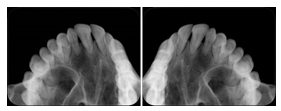

Intra-oral radiography typically involves acquisition of multiple images of various parts of the dentition. Many digital radiographic systems offer customized templates that are used for displaying the images in a study on the screen. These templates may also be referred to as mounts or view sets. The Structured Display Object represents a standard method of encoding and exchanging the layout and intended display of Structured Displays. A structured display object created in this manner could be stored with a study and exchanged with images to allow for complete reproduction of the original exam.

3. A dental provider wishes to capture a series of DICOM IO images for the patient’s dentition. The tooth morphology, teeth are divided into molars, premolars, canines and incisors, and a number of images for each jaw. The anatomic information was captured utilizing the triplet of schema. This standard code sequence is based on ISO 3950-2010, Dentistry - Designation system for teeth and areas of the oral cavity.

In most standard cases, images are oriented in structured layouts. These structured displays are useful to be shared between providers for reference purposes.

Table OO.1.1-1 shows structured display standard templates, where Viewset ID is based on the Japanese Society for Oral and Maxillofacial Radiology (JSOMR) classification provided by JIRA (Japan Medical Imaging and Radiological Systems Industries Association, www.jira-net.or.jp). Expected or typical teeth to be imaged location, region and designation codes are based on ISO 3950-2010, Dentistry - Designation system for teeth and areas of the oral cavity. For all the hanging protocols listed in OO.1.1-1, the value to use for Hanging Protocol Creator (0072,0008) is "JSOMR" and the value to use for Hanging Protocol Name (0072,0002) does not include "JSOMR" (e.g., "DL-S001A", not "JSOMR DL-S001A").